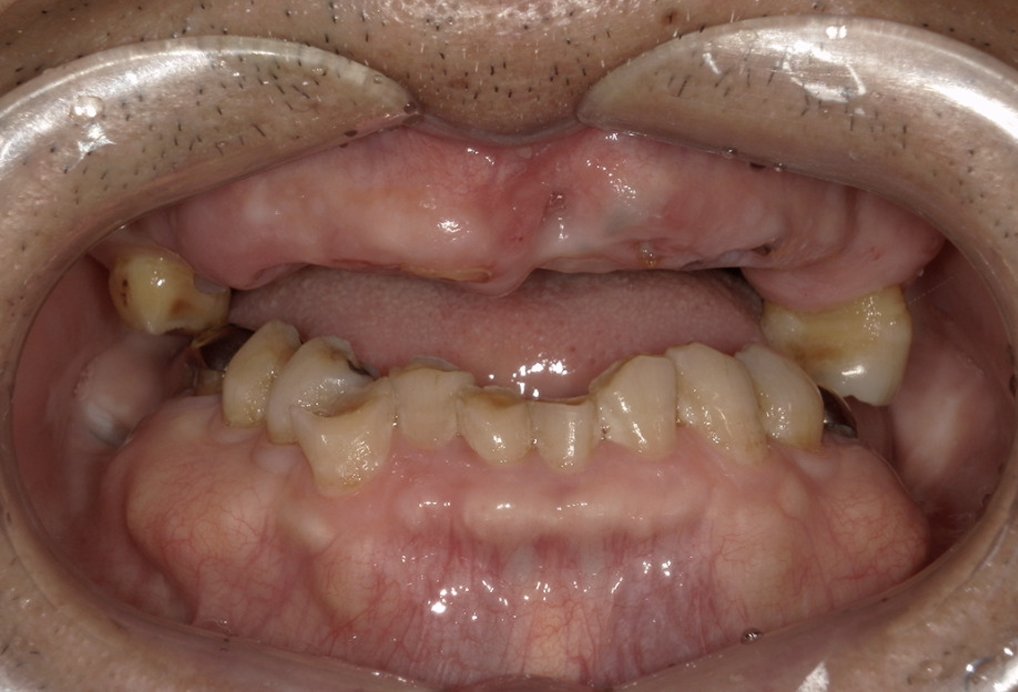

| 主訴 | 歯がグラグラして噛めない |

|---|---|

| 治療内容 | 上顎、下顎に対するインプラント治療 |

| 治療期間 | 1日 |

| 治療費 | 409万2千円 |

| 治療 リスク | 最終的な歯が入るまでは仮歯になります。 |